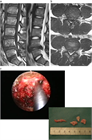

1. ヘルニアのサイズが大きいものや、遊離脱出したものや、MRIでリング状に造影されるものは高率に自然退縮する(ガイドライン推奨grade B)。